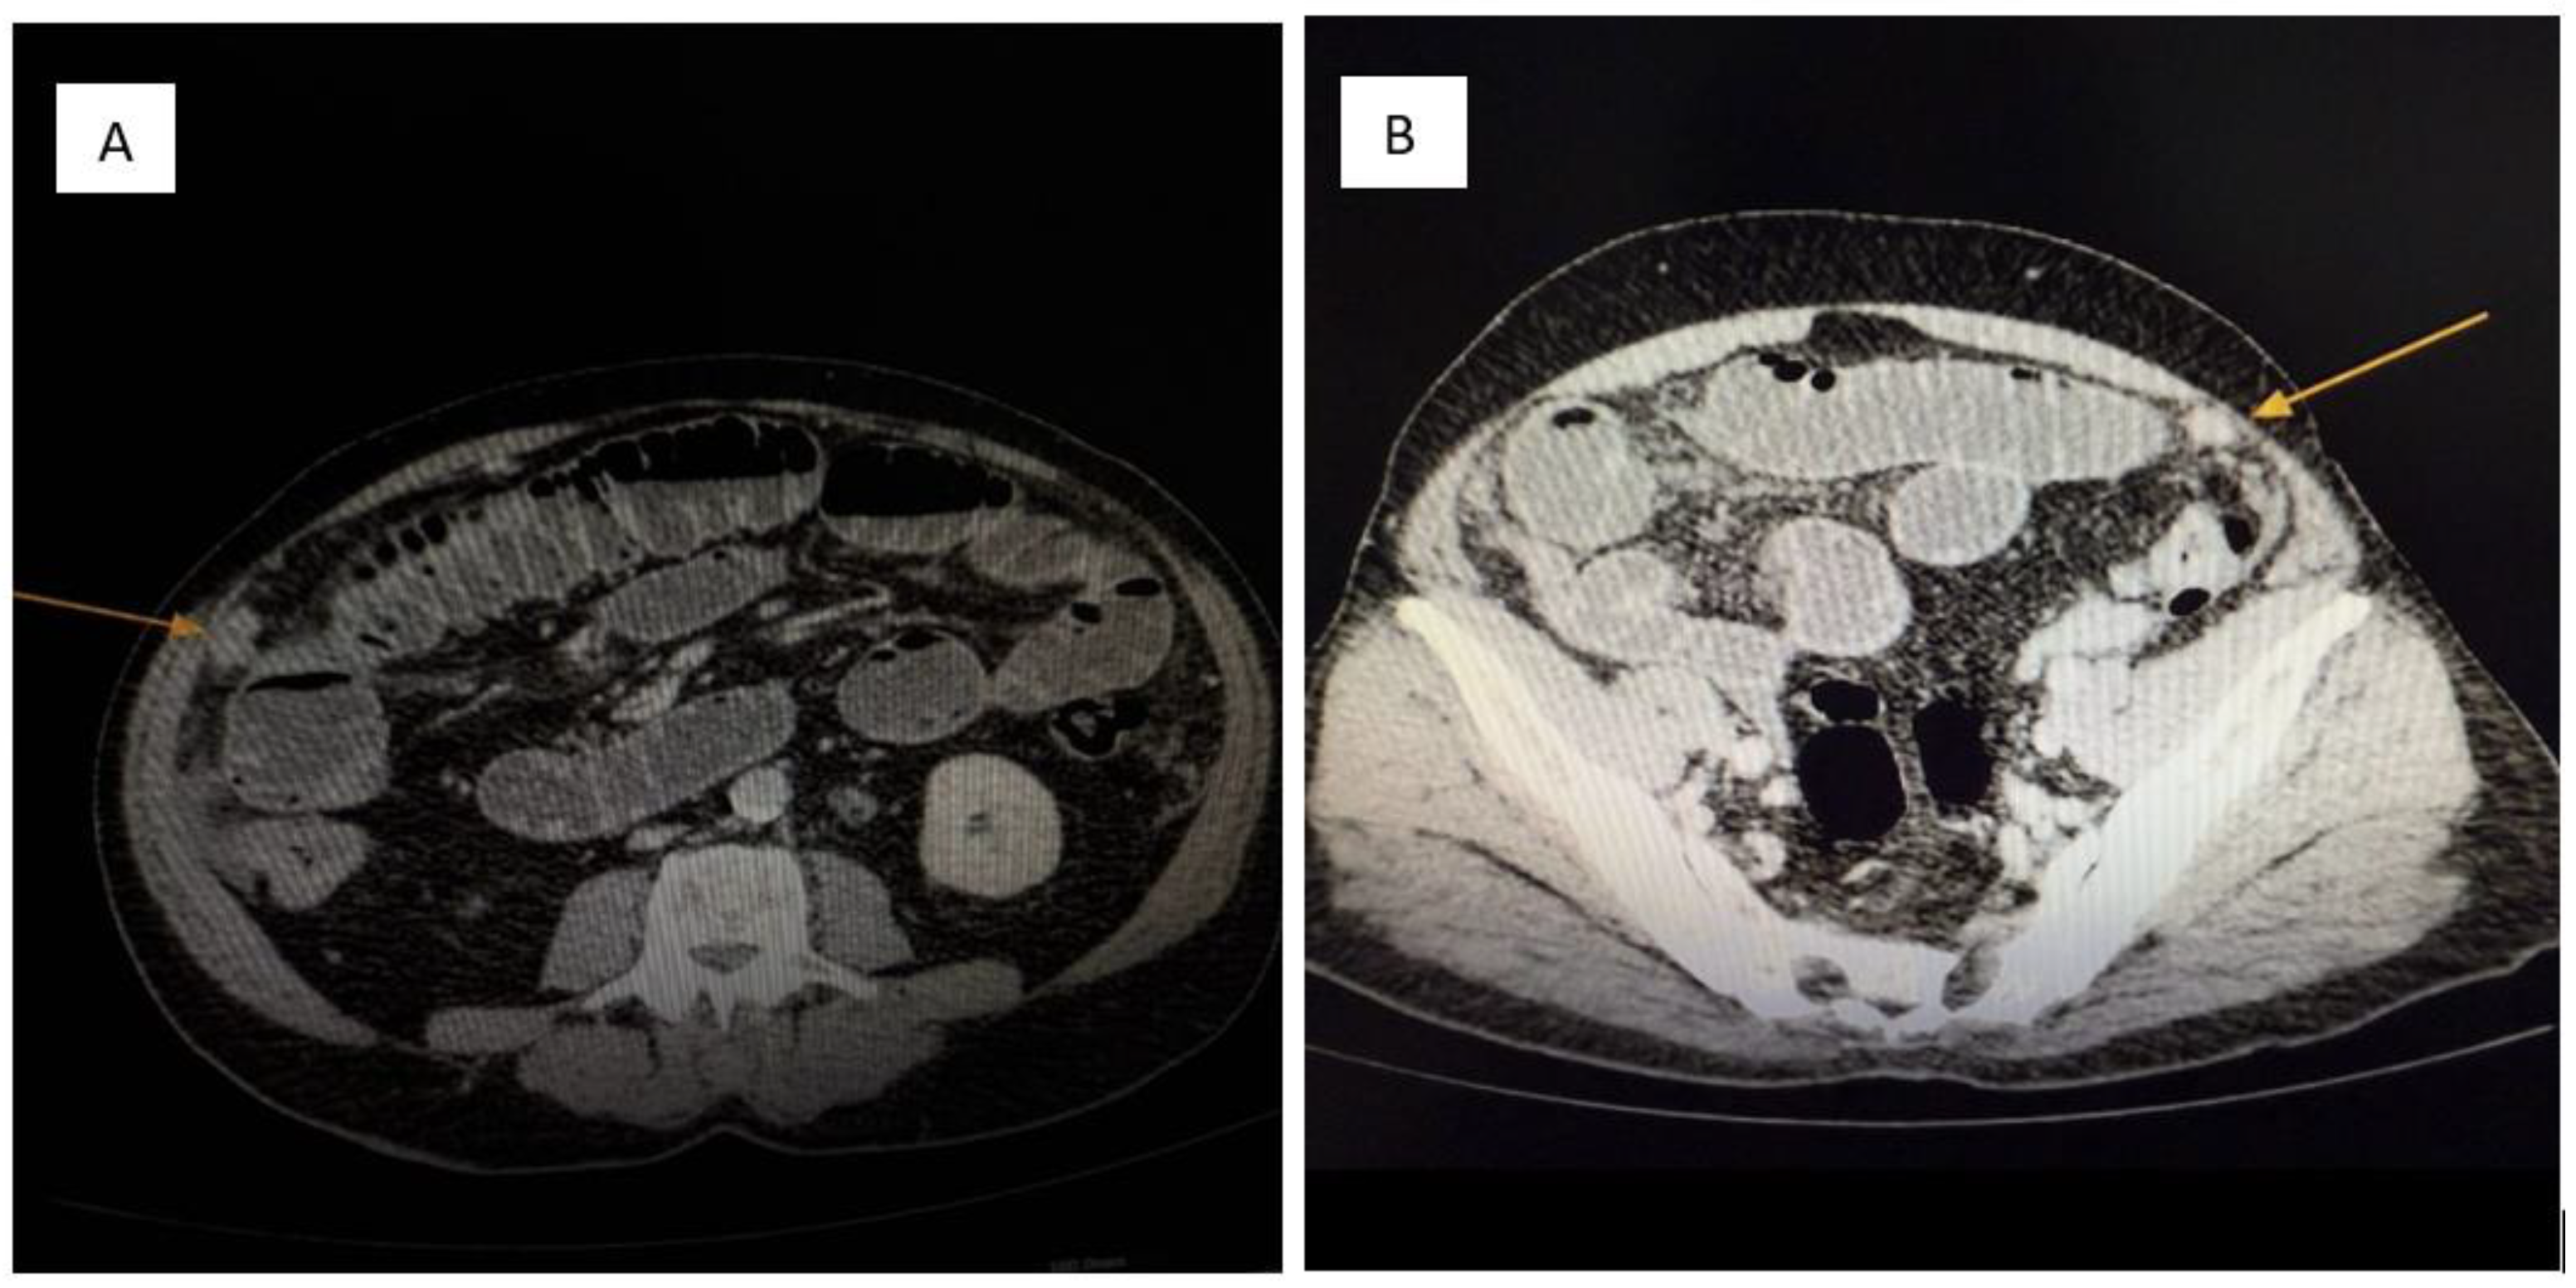

• Significant ascites and diffuse peritoneal nodular thickening suggestive of carcinomatosis (Figure 2).

Figure 2. (A,B): Contrast-enhanced abdominal CT. Multiple soft-tissue density nodules (yellow arrow) are diffusely distributed throughout the peritoneal cavity, consistent with metastatic involvement of the parietal peritoneum. The pattern and morphology of these lesions support a diagnosis of peritoneal carcinomatosis (yellow arrow) secondary to a neuroendocrine tumor.